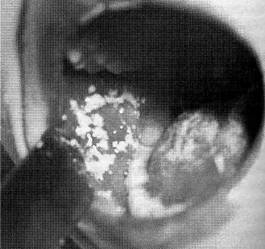

| I. Рис. 144. Кандпдозная инфекция. Наложение на слизистой оболочке щеки и языке — «молочница». |

или инфекционных заболеваний. Начинается стоматит с сухости и гиперемии слизистых оболочек, потери аппетита, небольшого ухудшения общего состояния. При первичном стоматите осмотр полости рта выявляет творожистые белые или кремовые наложения, располагающиеся на слизистой оболочке щек (рис. 144), десен, твердого и мягкого неба (рис. 145), внутренней поверхности губ. При вторичном стоматите поражения более глубокие и наложения на слизистой оболочке полости рта более толстые и плотные, чем при первичном процессе; отмечаются эрозии и изъязвления слизистой оболочки. В части случаев стоматит проявляется только гиперемией слизистой оболочки полости рта без инфильтративной реакции. У некоторых больных стоматиты приобретают форму язвенного процесса с поражением твердого неба и становятся причиной генерализованного кавдидоза.